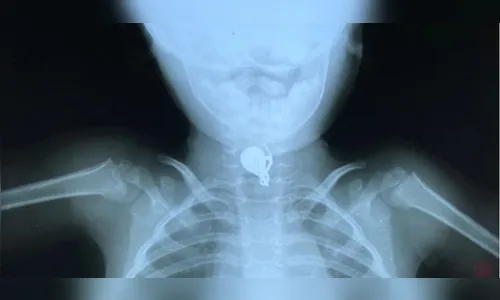

De acordo com as informações do site GMC Online, a criança engoliu um brinco. O procedimento de retirada do objeto foi realizado no Hospital Universitário (HU) da cidade.

A menina havia engolido o brinco da avó e o objeto ficou parado no esôfago dela. A família da vítima é do município de Paraíso do Norte, na região Noroeste, e a menina foi encaminhada para Maringá para retirar o brinco.

A equipe médica notou o local onde estava o objeto após analisar um exame de raio X. A criança já recebeu alta hospitalar.